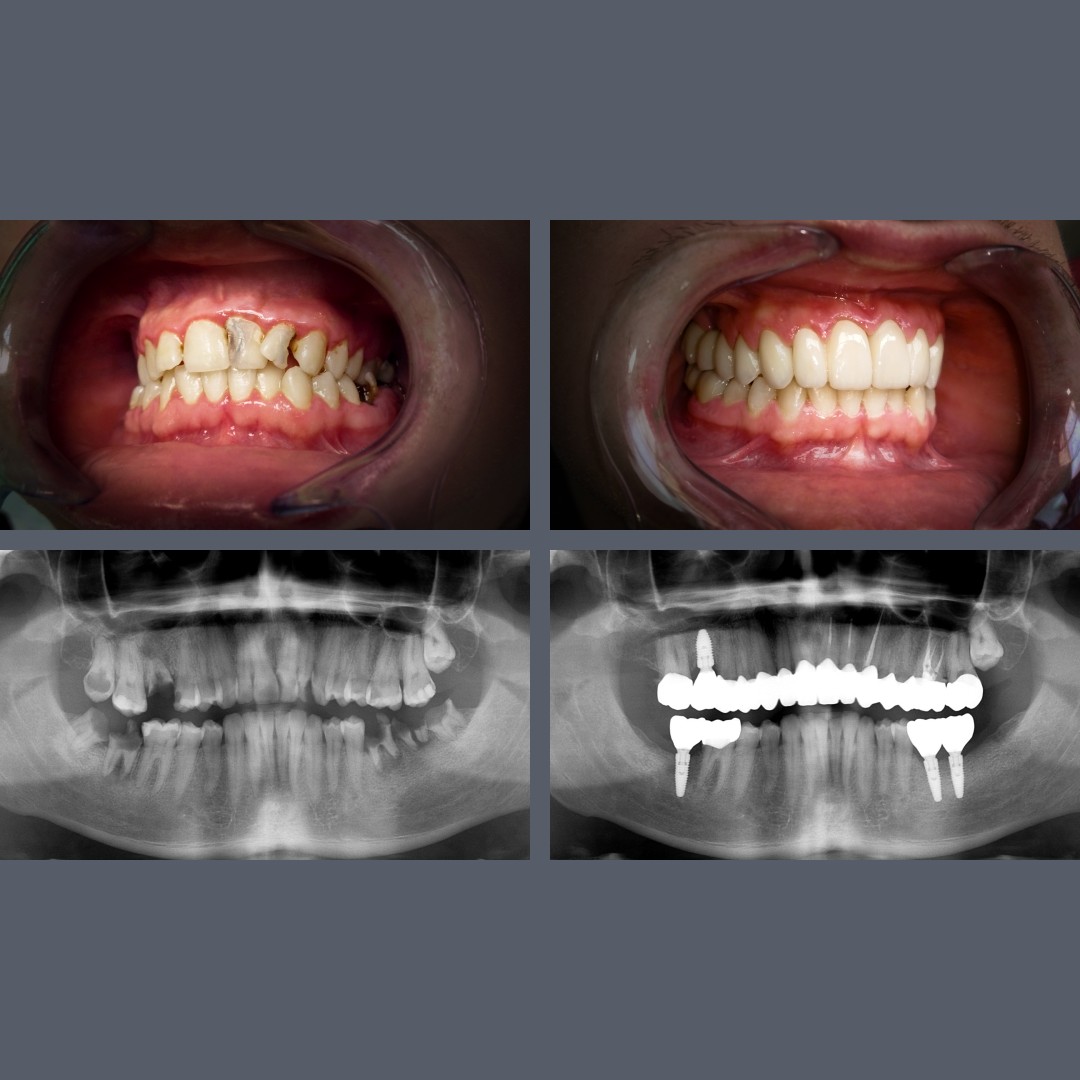

before-after

Full-Arch Aesthetic Restoration with Zirconia Crowns and Bridges for a Harmonious Smile

Treatment: Alternative Solutions